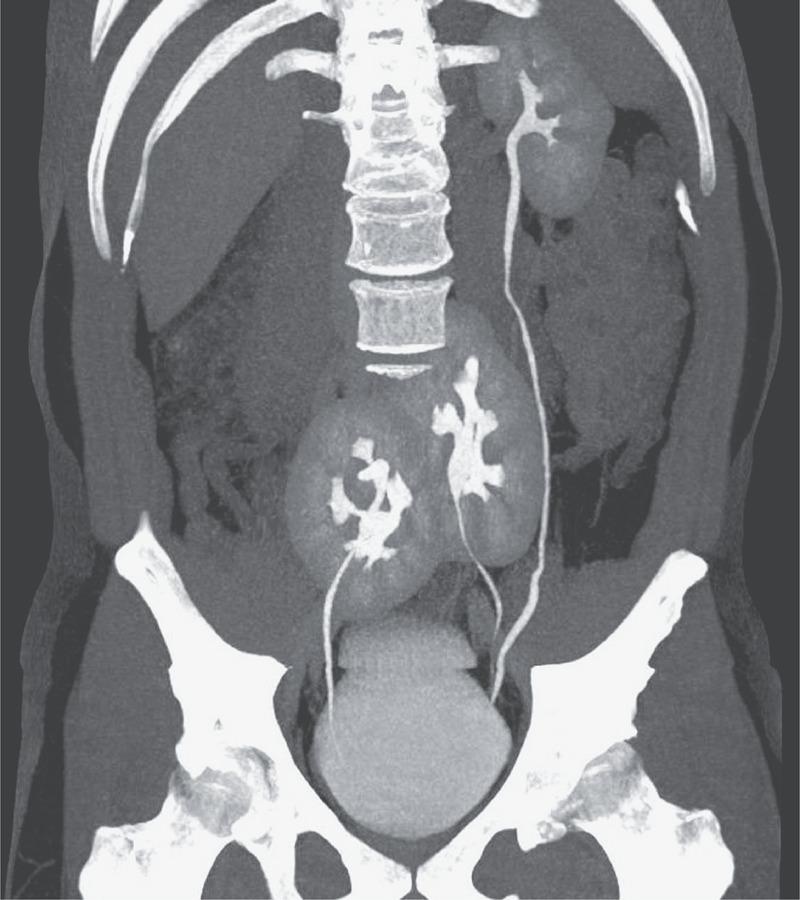

Medicii au explicat că pacientul avea un rinichi normal în partea stângă și alți doi rinichii lipiți, situați în zona pelvisului. Deși lipiți, cei doi rinichi din pelvis aveau propriile lor uretere, care îi lega direct de vezică, prin urmare pacientul avea trei rinichi și trei uretere.

„N-am văzut niciodată așa ceva”, a declarat Renato Foresto, unul dintre autorii raportului publicat în The New England Journal of Medicine. Medicii au ajuns la concluzia că cei trei rinichii erau în bună stare și funcționau fără anomalii.

Astfel, pacientul va putea continua să trăiască cu trei rinichi. Cel de-al treilea rinichi este mai mic, dar nu dă niciun fel de simptome și nu va necesita o intervenție chirurghicală pentru a fi extirpat.